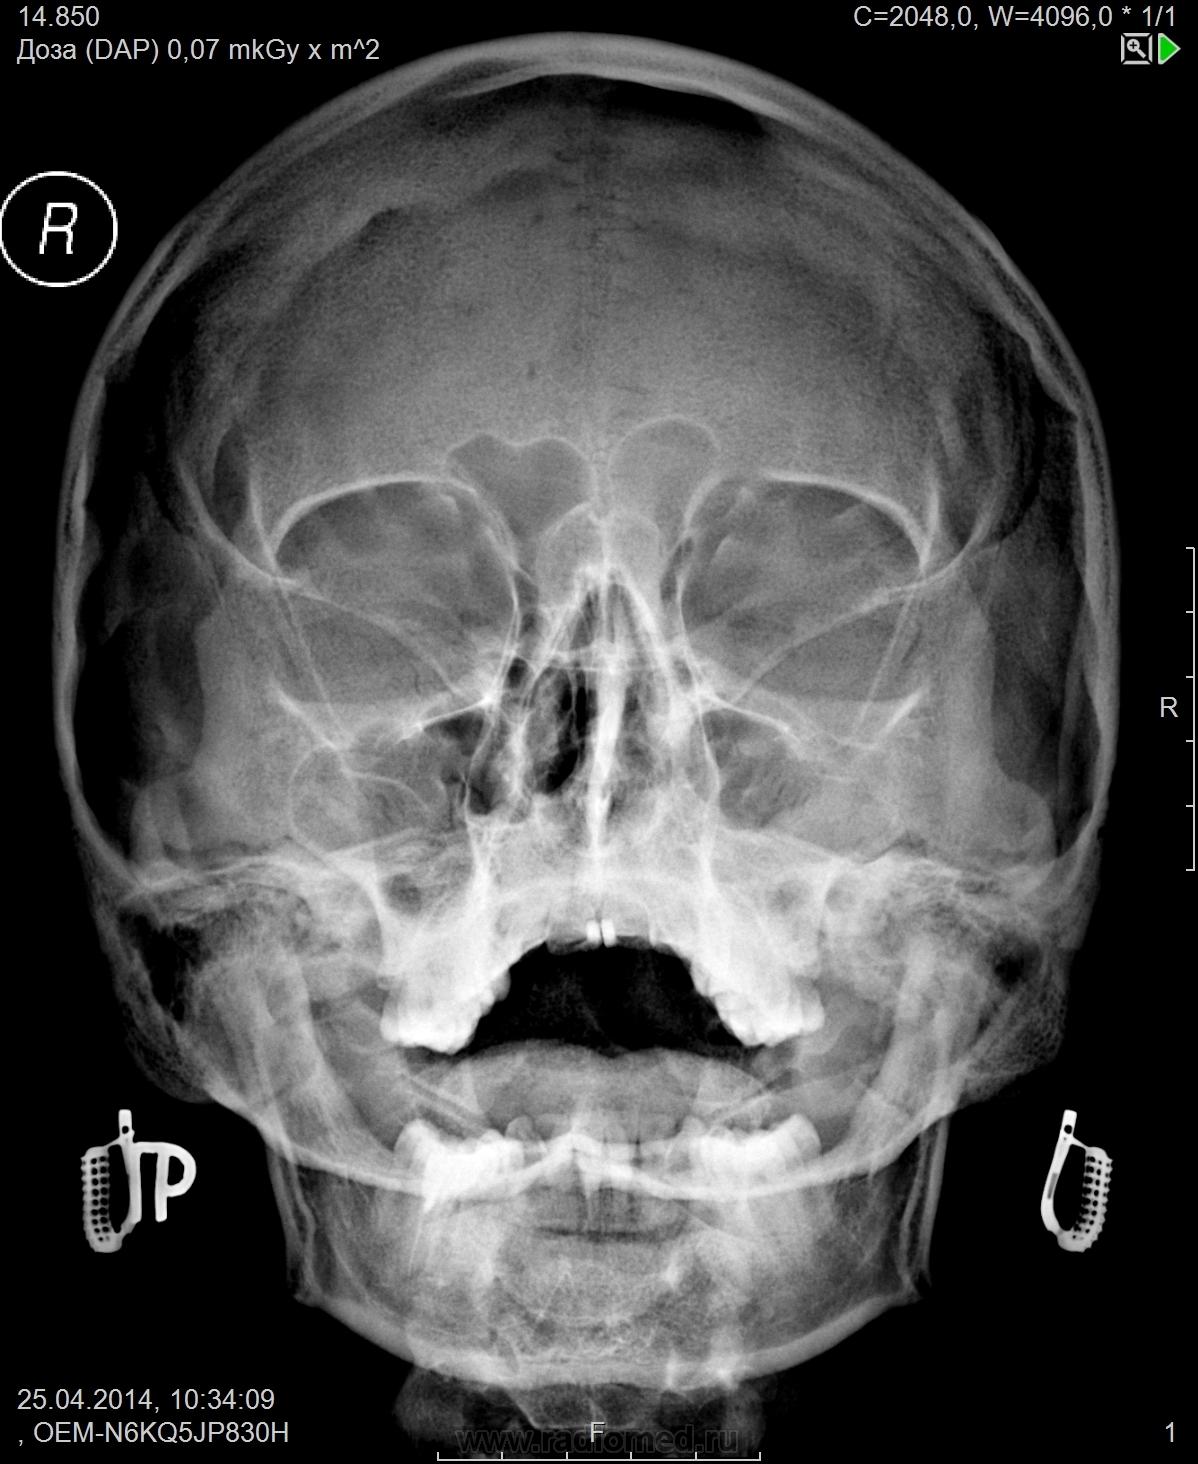

неправильная укладка - наслоение пирамиды височных костей на пазухи.

при правильной укладки либо пристеночное снижение пневматизации левой в\ч пазухи либо будет норма

пневматизация левой в/ч пазухи снижена

Согласен.Но я бы ешё добавил пристеночное снижение пневматизации левой лобной пазухи.

отмечается снижение воздушности в левой верхней челюстной пазухе за счет отека слизистой оболочки. Лобные пазухи и клетки решетчатого лабиринта не затемнены. Слизистая носовых ходов отечная. Заключение: Гайморит слева в фазе отека слизистой оболочки.

Ну, и признаки ринита можно вынести, коли о них говорим.)

как вы дифферинцируете отек от гиперплазии слизистой (хоть в пазухах, хоть в полости носа) по рентгенограмме?, думаю это пререготива клинициста + КТ или МРТ.

Ну, прежде всего, слежу за укладкой. А так, утолщение слизистой в левой в/ч пазухе и пристеночное снижение пневматизации в левой половине лобной))

Укладка - это главное, ага.)) А на фоне снижения пневматизации в левой лобной, может, жидкость усмотрели Вы, как и я?)

Лев. пристеночный гайморит, ринит